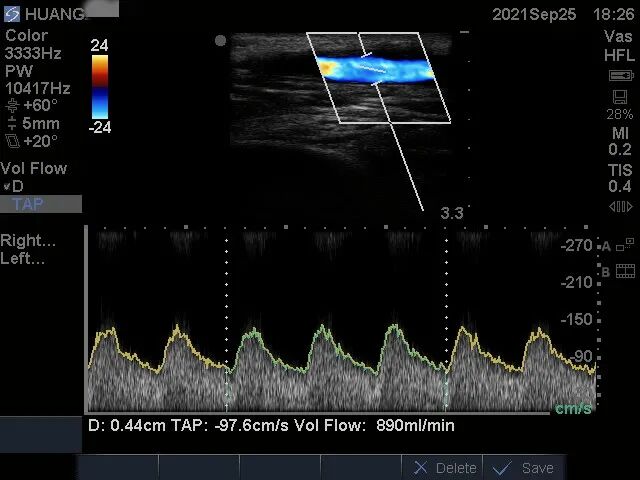

患者來院后,醫(yī)生為其查體,左上臂為人工血管動(dòng)靜脈內(nèi)瘺術(shù)后,觸診可及“U”型人工血管內(nèi)瘺成條索狀,質(zhì)硬,無法觸及震顫及聽及血管雜音,考慮人工血管動(dòng)靜脈內(nèi)瘺急性閉塞。而急診彩超也提示:人工血管內(nèi)充滿血栓,無血流,同時(shí)合并回流貴要靜脈狹窄(圖1、圖2),遂收住院擬行動(dòng)靜脈內(nèi)瘺經(jīng)皮球囊擴(kuò)張血管成形術(shù)+血栓取栓術(shù)。

圖1:術(shù)前彩超報(bào)告

術(shù)后彩超示:吻合口狹窄消失,上肢人工血管動(dòng)靜脈內(nèi)瘺通暢,震顫及雜音良好,測血流量890ml/min(圖3)。

圖3:術(shù)后血流量